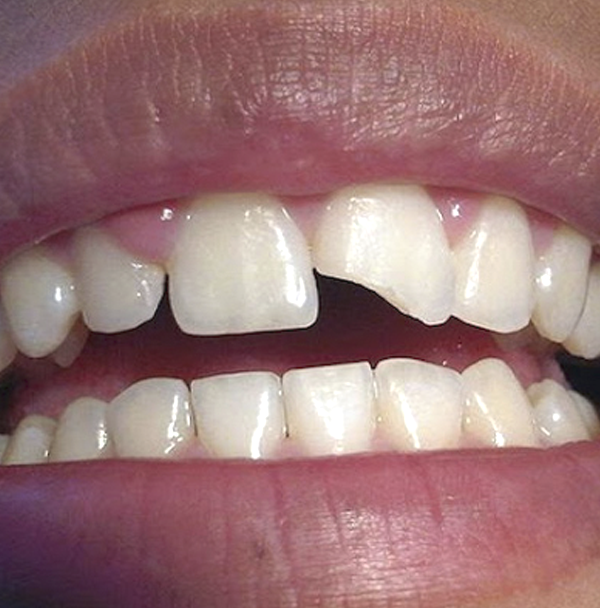

Fracturas dentales

Son roturas de una pieza dental, muchas veces tras sufrir un traumatismo.

Existen diferentes tipos de fractura dental, en función de si solo abarca el esmalte, el esmalte y la dentina o si, además del esmalte y la dentina, también afecta el nervio.

Si tuviste un accidente y te ocasionó una fractura dental no lo dejes así, atiéndete.